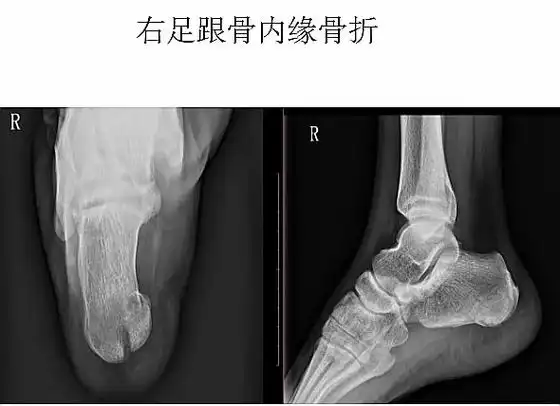

跟骨侧轴位x线影像技术.分享#医学影像 #放射技术 #医学小 - 抖音